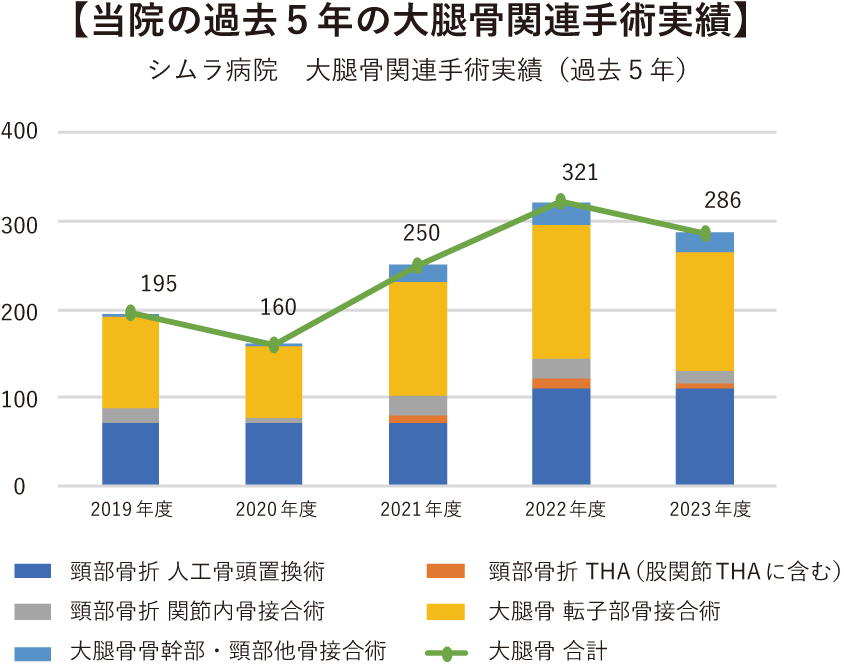

ご高齢の患者さまは、骨粗鬆症等により軽度の転倒などでも骨折する場合があります。一度骨折すると再骨折する可能性が高まり、脆弱性骨折により健康度が悪化します。なかでも大腿骨近位部骨折や椎体骨折は、以前の健康状態に回復することは困難になります。また、骨折後の死亡率が高くなるデータが確認されています。

下の図は、大腿骨近位部骨折をすると6年の間に40%近くの患者さまが亡くなっていることを示しています。

これらの報告は、骨折による活動性の低下から嚥下機能を含む筋力低下・環境の変化による認知症の発症や増悪・せん妄が出現する可能性があることや、心不全・肺・脳血管障害・全身の感染症などにより命を脅かす合併症を起こす可能性があることを示しています。早期手術が予後にはよいと知られていることから、当院では早期に手術を行うことに積極的に取り組んでおります。